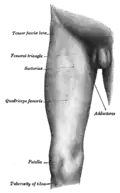

Aspecto medial e frontal da coxa direita.

Aspecto medial e frontal da coxa direita.